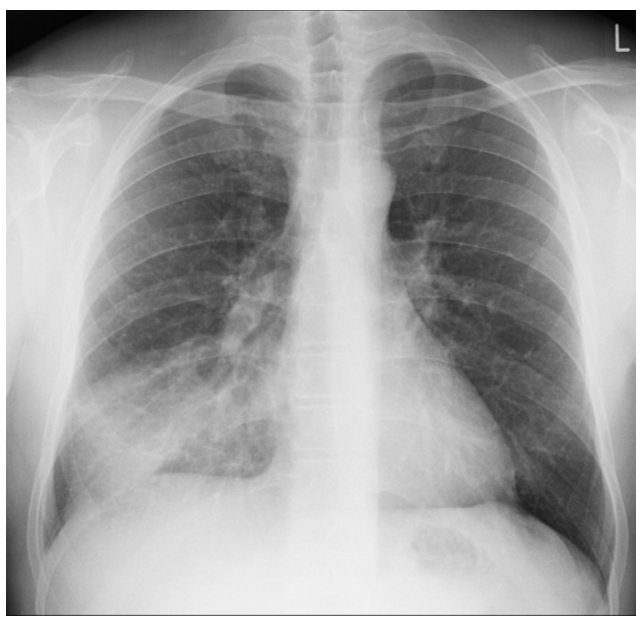

Interne de garde aux urgences, vous recevez monsieur P, un patient de 67 ans, consultant pour toux fébrile depuis 3 jours. Nous sommes fin novembre.

Vous lui avez réalisé dans ce contexte une radiographie thoracique.

Murmure vésiculaire audible, diminuée à droite. Crépitants au niveau du champ pulmonaire droit.